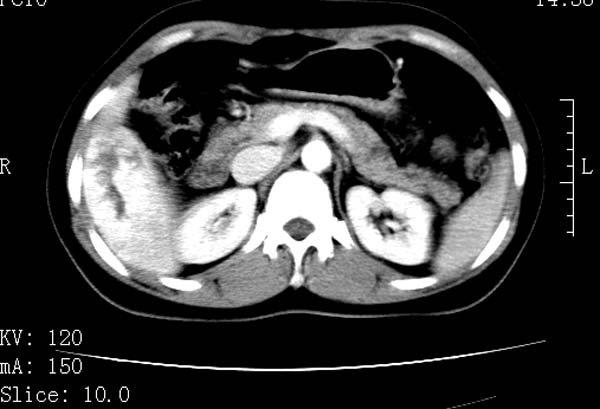

标题: CT22086:女44岁 肝右叶占位增强示巨大血管瘤,门脉期发现小 [打印本页]

标题: CT22086:女44岁 肝右叶占位增强示巨大血管瘤,门脉期发现小

请大家观察一下小灶   发表意见,谢谢

小病灶也是血管瘤。

支持肝右叶血管瘤诊断。小灶是否为囊肿,

支持肝右叶血管瘤诊断。 小病灶亦考虑血管瘤改变。温习一下:

肝海绵状血管瘤ct平扫常呈均匀低密度,与邻近血管密度相仿。在脂肪肝背景下可呈相对高密度。在增强扫描时,一般早期(动脉期)呈周边结节状或弧形强化,其密度与同层面的血管密度相仿,随着时间延迟向中央渐进性充填,注药后5~7分钟,逐渐扩大至全瘤强化,强化密度逐渐降至稍高于或等于正常肝脏。大的血管瘤往往中央有星形、大的低密度区,可以为纤维化或囊性变所致,纤维化成分可在延迟2 o分钟时完全充填,呈等密度,但囊变区则不会强化。不典型ct表现常见于≤3 cm的小血管瘤。小的血管瘤可以在动脉期即呈全部致密的均匀强化,不呈典型的周边结节状强化表现,但其密度往往较高,与主动脉相仿,在延迟期呈高或等密度。其他不典型的ct表现有:增强扫描强化不明显,呈点状较轻程度的强化,充填慢,可能与供血动脉较细和较大的血管间隙有关以及中央先强化等。

延迟扫描三个病灶都呈等密度改变。肝多发血管瘤,较典型。